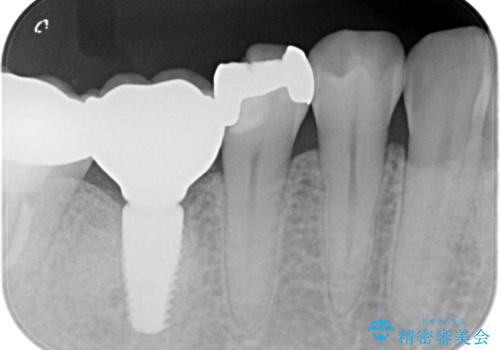

- 「食事をしていたら歯が欠けた」を主訴に来院された患者様です。

メタルインレーが入っており、インレーとの境の歯質が欠けている状態でした。

不幸中の幸いで欠けているところが根っこよりも上だったため、オールセラミッククラウンで治療を行いました。

銀歯を除去後、やはり銀歯の下は虫歯になっていましたので、虫歯を除去した後にオールセラミッククラウンで被せました。